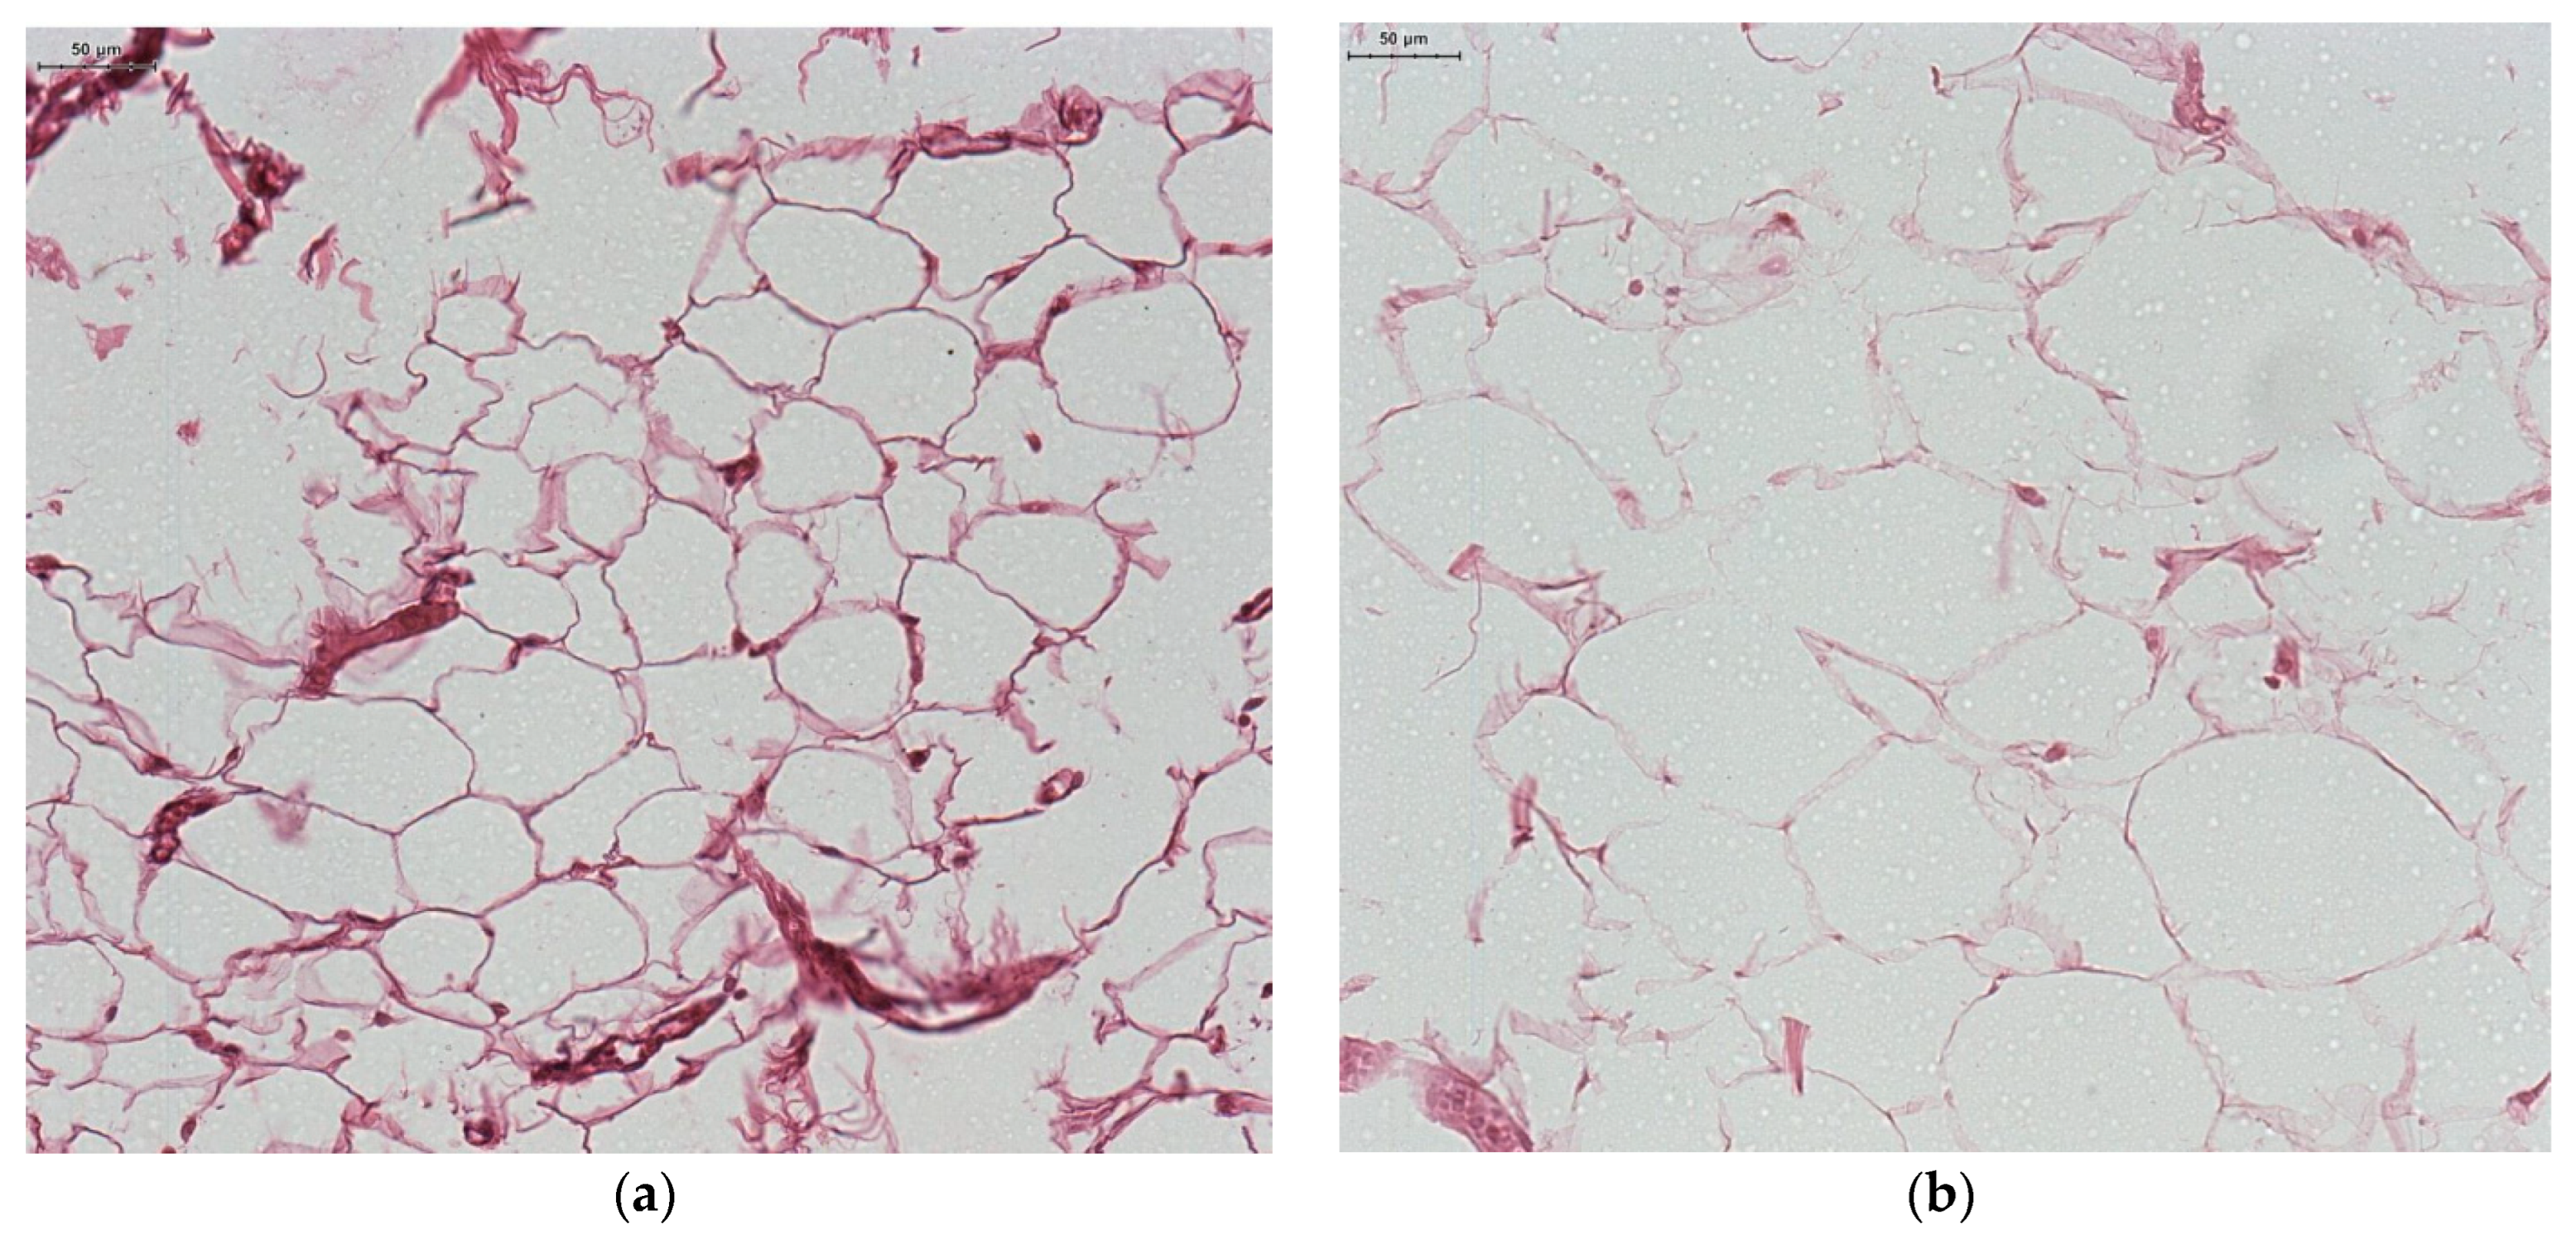

Histopathological Study

| Adipocyte size (µm) | 6.62 ± 1.78 | 9.34 ± 2.11 | 0.027 |

| Blood vessel wall thickness (µm) | 6.92 ± 1.48 | 8.79 ± 2.12 | 0.0001 |